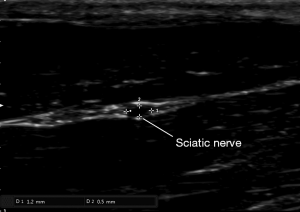

Sciatic nerve’s diameter and circumference measurement with ultrasound guidance

After anesthesia and depilation, we used a L18-4 linear array probe (frequency range 4–18 MHz) (Sonimage HS1, Konica Minolta Co., China) to measure the diameter and circumference of nerve and to locate the stimulation electrode. The detection depth of the screen was 1cm. The sciatic nerve of rat is mainly composed of the lumbar spinal nerve (L4–L6), after travelling in front of the sacroiliac joint and bypassing the great trochanter of the femur and reaching the rear of the femur, the nerve finally divides into three major branches, namely the common peroneal nerve, tibial nerve and sural nerve.

Anatomical measurement data showed that the femur length of SD rats was about 3 cm, the length of the posterior femur segment of the sciatic nerve trunk was about 1.7 cm, and the midpoint of the femur was about 0.5 cm from the upper margin of the sciatic nerve trunk, that is, the beginning of the branch of the sciatic nerve trunk was below the midpoint of the femur. So the probe was placed in the greater trochanter of the femur and moved downwards. Below the midpoint of the femur, the probe was placed perpendicular to the femur to measure the diameter and circumference of the sciatic nerve (Figure 2).